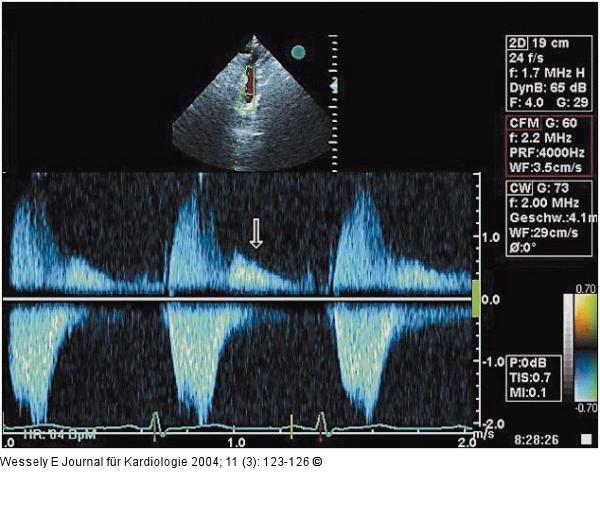

Abbildung 5: Aortenklappeninsuffizienz - Endokarditis Suprasternale CW-Dopplerregistrierung des systolischen und diastolischen Flusses der Aorta descendens |

Suprasternale CW-Dopplerregistrierung des systolischen und diastolischen Flusses der Aorta descendens |